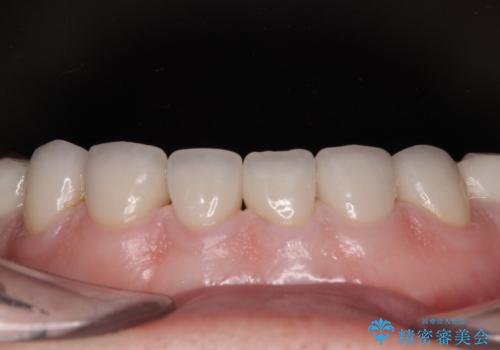

口を開けたときに見える範囲をオールセラミッククラウンとし、とても自然な口元に仕上げることができました。